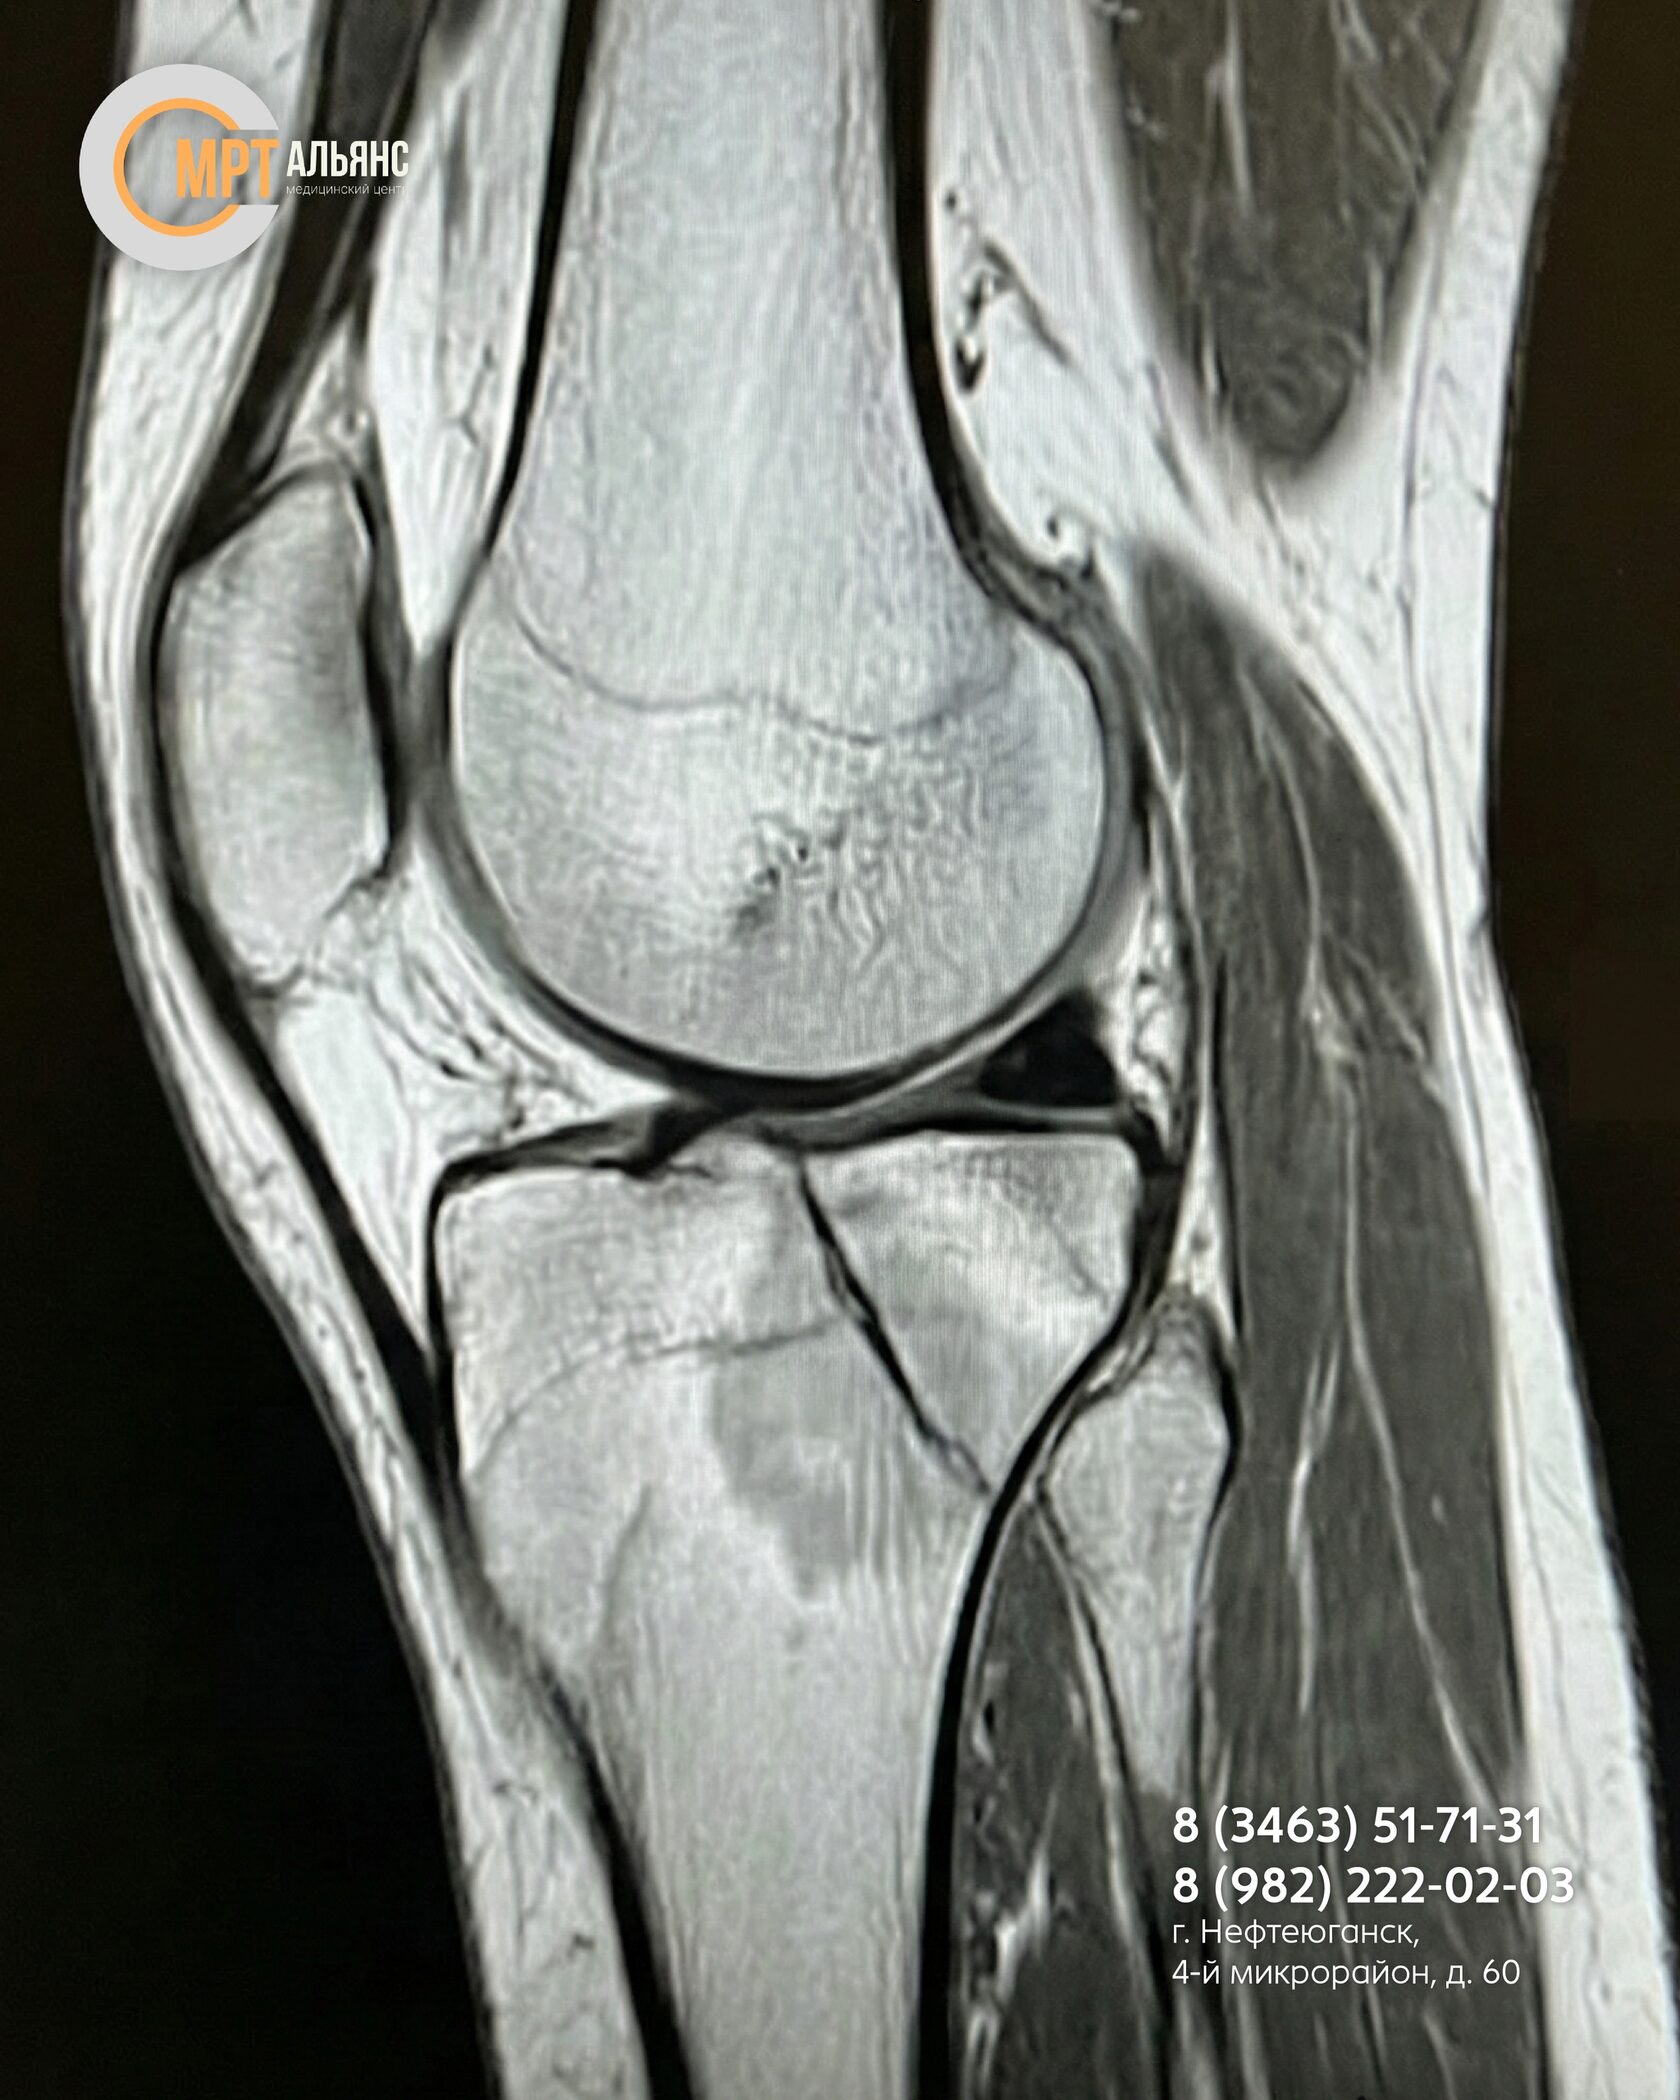

Наш томограф Philips Achieva 1.5T — современное оборудование экспертного класса. Он видит то, что скрыто от других методов:

Это критически важно при травмах суставов: колена, плеча, голеностопа, позвоночника — когда «просто перелом» может оказаться сложной комбинированной травмой.

- Микротрещины костей

- Повреждения хрящей и менисков

- Разрывы связок, сухожилий и мышц

- Воспаления и отеки, мешающие заживлению